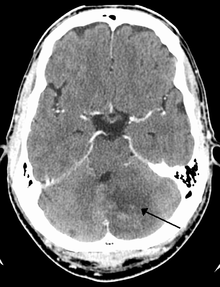

Left sided cerebellar stroke due to occlusion of a vertebral artery

Cerebellar stroke syndrome is a condition in which the circulation to the cerebellum is impaired due to a lesion of the superior cerebellar artery, anterior inferior cerebellar artery or the posterior inferior cerebellar artery.[1]